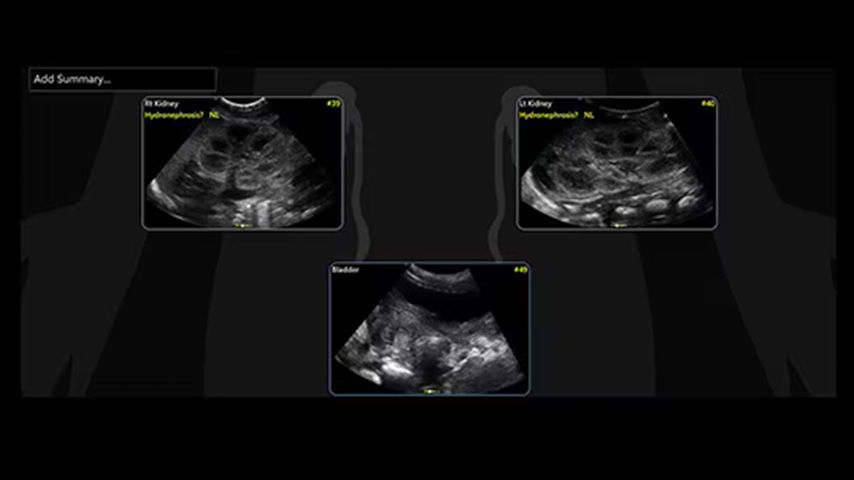

Quickly assess kidneys and the bladder with Renal Diagram

Simplify documentation and easy follow up for patients with suspected hydronephrosis. No need to type findings; simply assign a label from a pre-populated list that correlates with images.